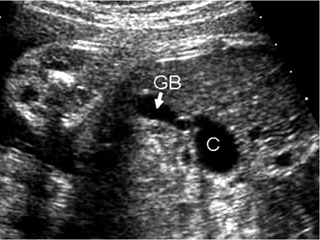

Κύστεις ωοθήκης

Είναι συχνές και ανευρίσκονται στο ένα τρίτο των νεογνών, παρόλο που είναι συνήθως

μικρές και ασυμπτωματικές. Οι εμβρυικές ωοθηκικές κύστεις είναι ορμονο-εξαρτώμενες

(από τη χοριακή γοναδοτροπίνη του πλακούντα) και έχουν την τάση να εμφανίζονται

μετά τις 25 εβδομάδες της κύησης (εικόνα 25). Είναι συχνές στις διαβητικές μητέρες

και στις μητέρες με Rhesus ευαισθητοποίηση, ως αποτέλεσμα της υπερπλασίας του

πλακούντα. Οι περισσότερες είναι καλοήθεις και υποχωρούν αυτόματα στη νεογνική

περίοδο.

| Εικόνα 25. Κύστη ωοθήκης (C). C: κύστη. GB: χοληδόχος κύστη. |